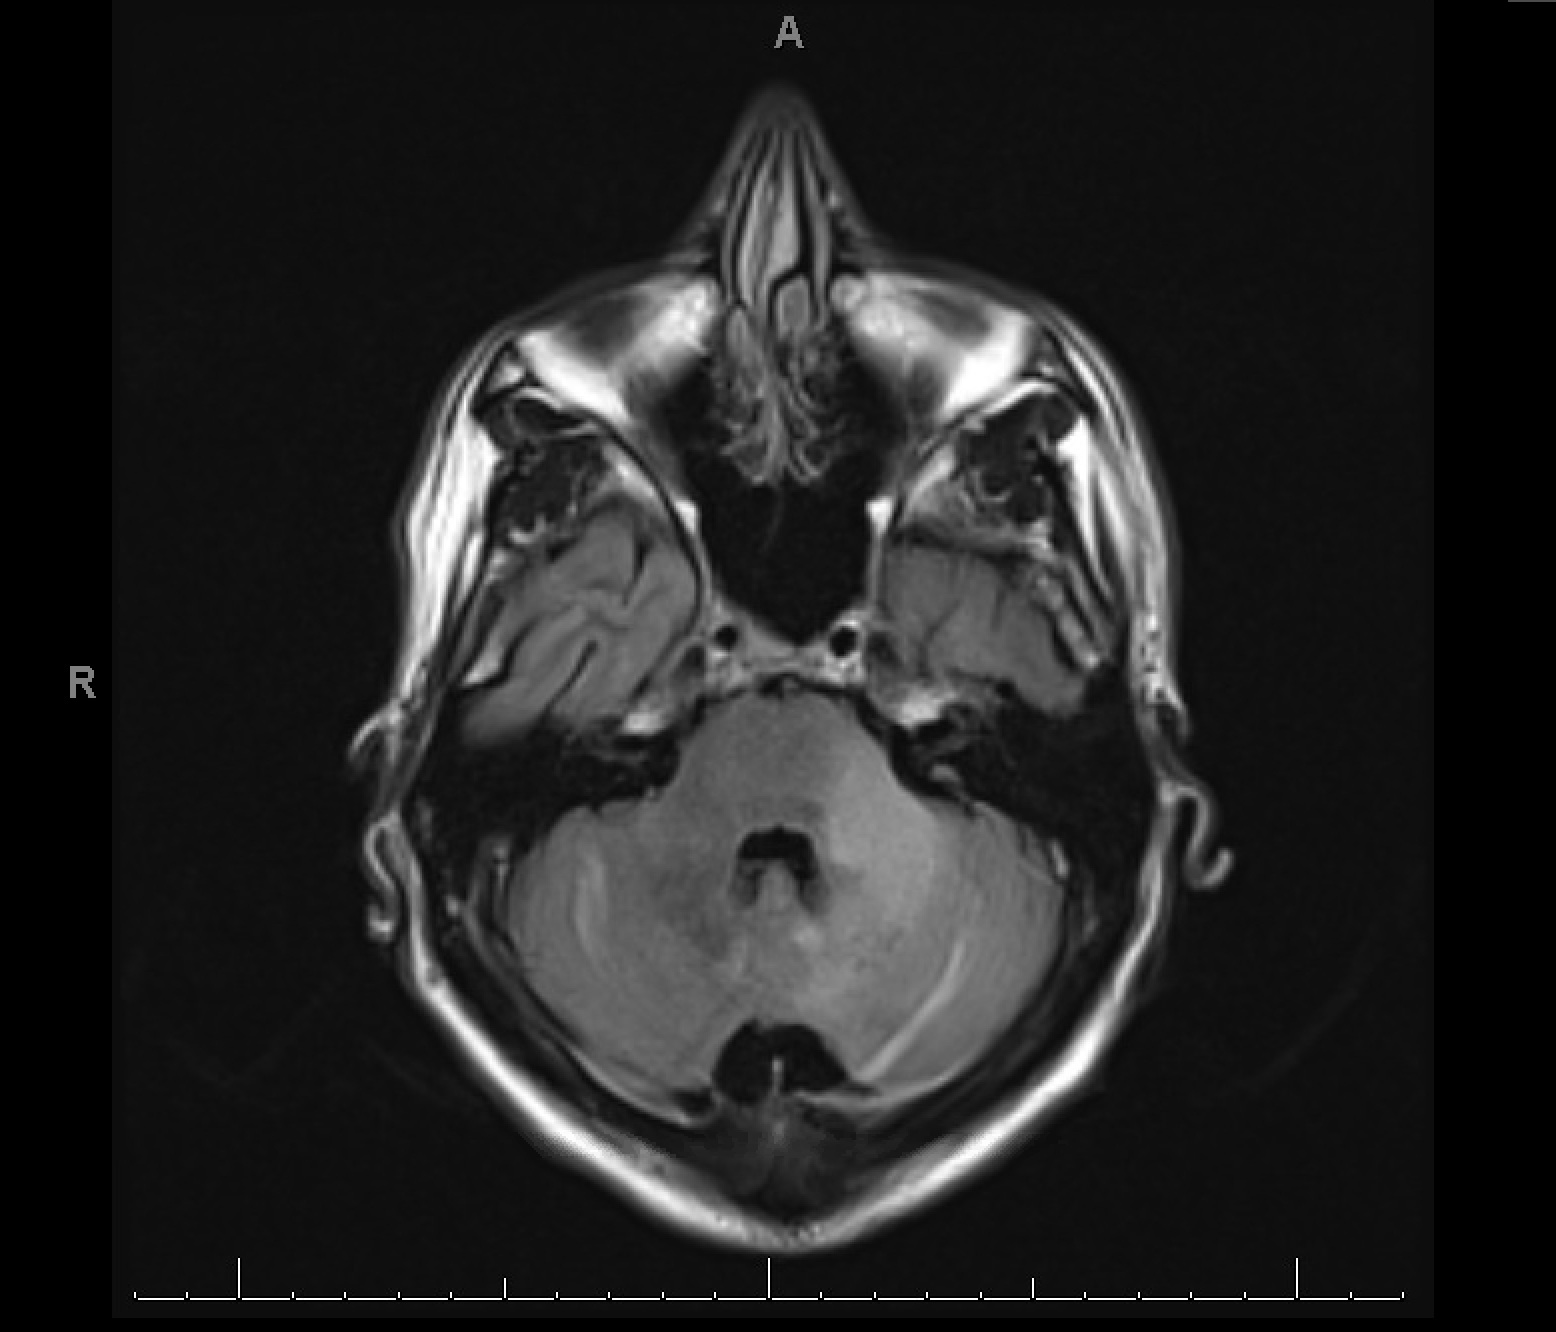

Case Presentation: A 33-year-old male without significant medical history experienced visual changes, left-sided tingling and weakness, vertigo, nausea, and mild expressive aphasia for 2 months. At that time, he had mild upper extremity tremor and was able to walk, drive, and perform activities of daily living. On physical exam, the patient demonstrated left upper extremity dysdiadochokinesia, bilateral upper extremity dysmetria, slowed speech, and extreme nausea and vomiting. Lower extremities showed bilateral dysdiadochokinesia although no dysmetria. He had moderate strength (3-4/5) throughout, although movements were limited by severe nausea. The patient denied intravenous drug use (IVDU) or male sexual partners, but reported having multiple female sexual partners.His primary care physician had ordered magnetic resonance imaging (MRI) for suspected multiple sclerosis, which showed demyelination and a large left cerebellar lesion with high signal intensity on T2/FLAIR. Smaller lesions with similar characteristics were present in the cortex of the right thalamus, bilateral occipital lobes, right parietal lobe, and left frontal lobe. In the inpatient setting, a human immunodeficiency virus (HIV) test was positive with a CD4 count of 35 cells/μL. Positive cerebrospinal fluid polymerase chain reaction for John Cunningham (JC) virus confirmed the diagnosis of progressive multifocal leukoencephalopathy (PML).